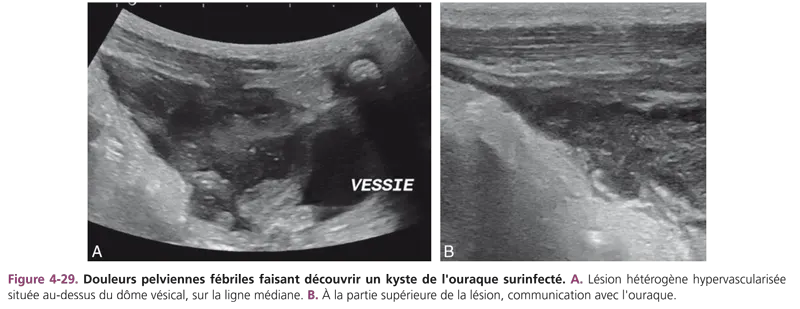

Tumeur ovarienne sécrétante Leur diagnostic est échographique, effectué sur la présence d’une masse ovarienne, d’aspect non spécifique, souvent hétérogène et volumineuse, complété par un scanner pour le bilan d’extension. La tumeur de la granulosa est la plus fréquente.

Le dysgerminome est la forme histologique la plus fréquente des tumeurs malignes de l’ovaire à l’âge pédiatrique. Il est, le plus souvent, non sécrétant. Les autres tumeurs ovariennes sont très rares : tumeurs épithéliales (cystadénomes séreux et mucineux), tumeurs de la granulosa avec hyperoestrogénie (fig. 4-28), etc. [14]. Des localisations métastatiques ovariennes peuvent se voir lors des hémopathies malignes.